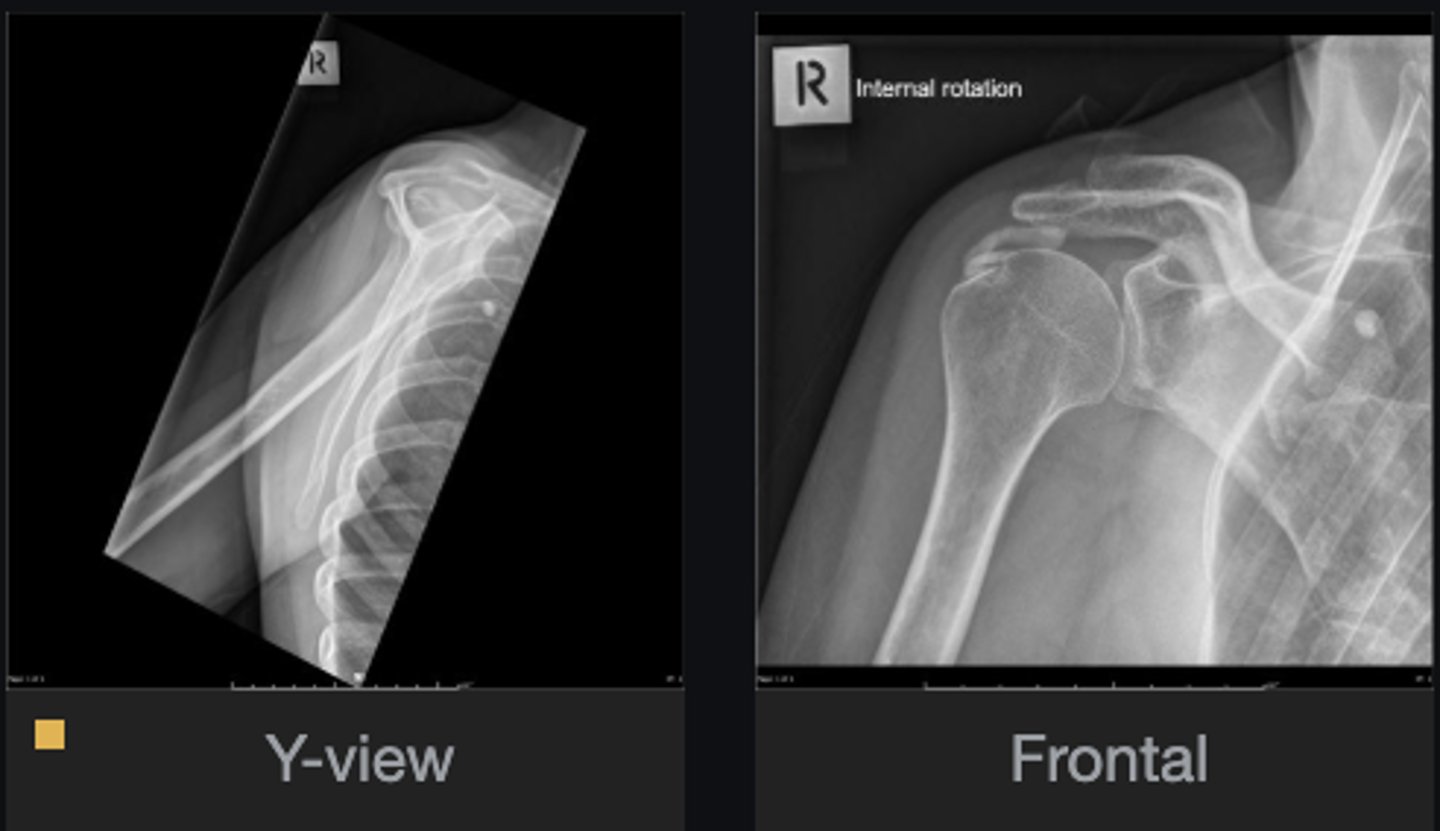

- Calcification of supraspinatus tendon

- Acromiohumeral interval enlarged

List the abnormal findings

Hydroxyapatite Deposition Disease

Diagnosis?

Supraspinatus

What tendon is involved?

Calcification in lung

Do you see anything else that is abnormal?